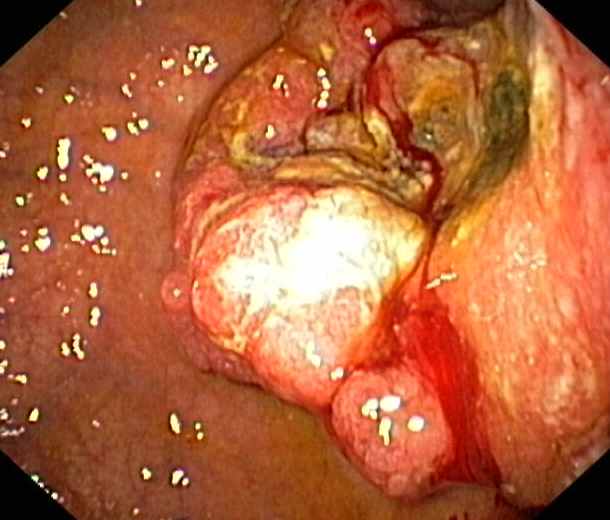

Caecum:

Cancer (Adenocarcinoma)